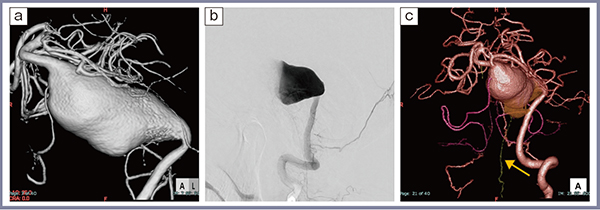

症例3(図3)は,50歳代,女性の内頸動脈瘤である。高精細CTでは,前脈絡叢動脈(ピンク),後交通動脈(Pcom,グリーン)の穿通枝が明瞭に描出されており,動脈瘤の内側に張り付くように走行していることを確認できる(図3 a)。前脈絡叢動脈はもちろん,Pcomの梗塞でも高次脳機能障害が生じうることから,これらの穿通枝を温存して治療を進めることが重要である。また,静脈展開については,本症例では主に下吻合静脈方向に灌流していることがわかる(図3 b)。ある程度の大きさの動脈瘤では,頸部確保が必要な状況に備えて頸部血管も同時に撮影している(図3 c)。プランニング画像(図3 d)では,視神経との関係をMRIとのフュージョン画像で作成し,血管や動脈瘤との位置関係,圧迫や癒着の強い部分を認識しやすく表示している。術野から見たイメージは,脳実質や前床突起を透過させることで周囲を理解しやすくなる。実際の手技では,想定どおりにPcomが認識でき,サクションデコンプレッション法で動脈瘤を収縮させてクリッピングした。ICG,内視鏡にて前脈絡叢動脈の温存を確認して手術を終了した。

症例4(図4)は,60歳代,男性で,脳底動脈巨大紡錘状動脈瘤である。まれな症例だが,破裂によるクモ膜下出血,血栓化や圧迫による脳幹障害を来す。治療法としては,血管内治療,バイパス術による血行再建,クリッピング,コイル塞栓術など外科的あるいは血管内治療が試みられるが,確立したものはなく脳神経外科の中でも最もチャレンジングな疾患の一つである。解離から始まり経過観察を続ける間に動脈瘤が拡大しドーム状を呈した(図4 a)。血管造影では動脈瘤内部の乱流の影響を受けて穿通枝の描出は難しい(図4 b)。高精細CTではドームの一部から分枝していると思われる穿通枝(前脊髄動脈:anterior spinal artery)が確認できた(図4 c↑)。

図3 症例3:内頸動脈瘤

図4 症例4:脳底動脈巨大紡錘状動脈瘤